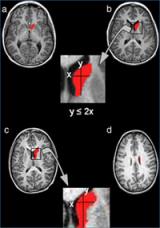

In red is the caudate nucleus, on top is the head and at the bottom the body. The formula indicates the method to separate the head from the body.

The first study cited by the “Consensus Report” was published in Psychiatry Research: Neuroimaging in 2008. The focus of the group’s research was on the caudate nucleus, one of the main brain structures associated with learning and memory. The caudate nucleus has three parts: the head, the body, and the tail. The research showed abnormalities in the caudate nucleus among patients with ADHD, while earlier literature described contradictory results as to what these abnormalities were. Dr Vilarroya’s group discovered that in patients with ADHD, there were abnormalities between the head and the body of the caudate nucleus, abnormalities that were not found in control subjects. With the development of a new method of segmenting the caudate nucleus between the head and the body, it was shown that patients with ADHD had a smaller right caudate nucleus, basically due to a reduction in the size of the body (and not the head) of the caudate nucleus.

Subsequent studies have sought to automatise the method for segmenting the caudate nucleus between the head and the body to allow a rapid and efficient use for clinical purposes. In this regard, two works have been published: one in the magazine Biomedical Engineering Online (2011), in which researchers have developed a automatised method for segmenting the caudate nucleus, based on an analysis of medical imaging and automatic learning techniques; and the other in the magazine Computerized Medical Imaging and Graphics (2012), in which researchers have optimised this method to separate the head from the body of the caudate nucleus, obtaining results that are very similar to those obtained in manual segmentation. With these new methods, the main brain structures can be characterised more rapidly and accurately and an analysis and early diagnosis given of ADHD.